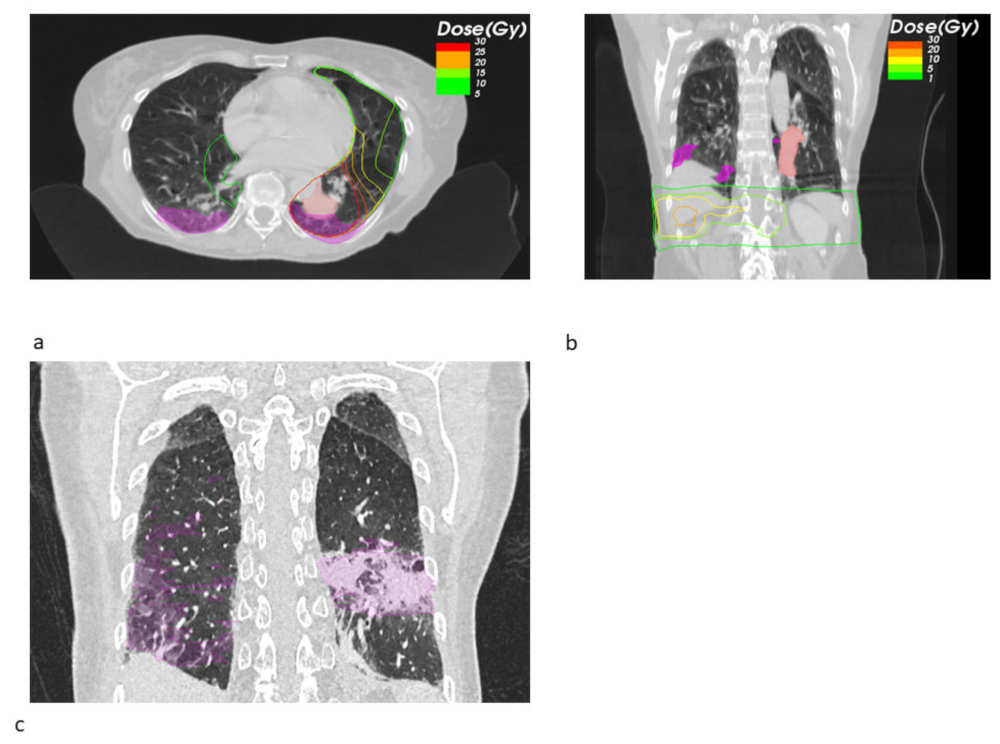

3. Results